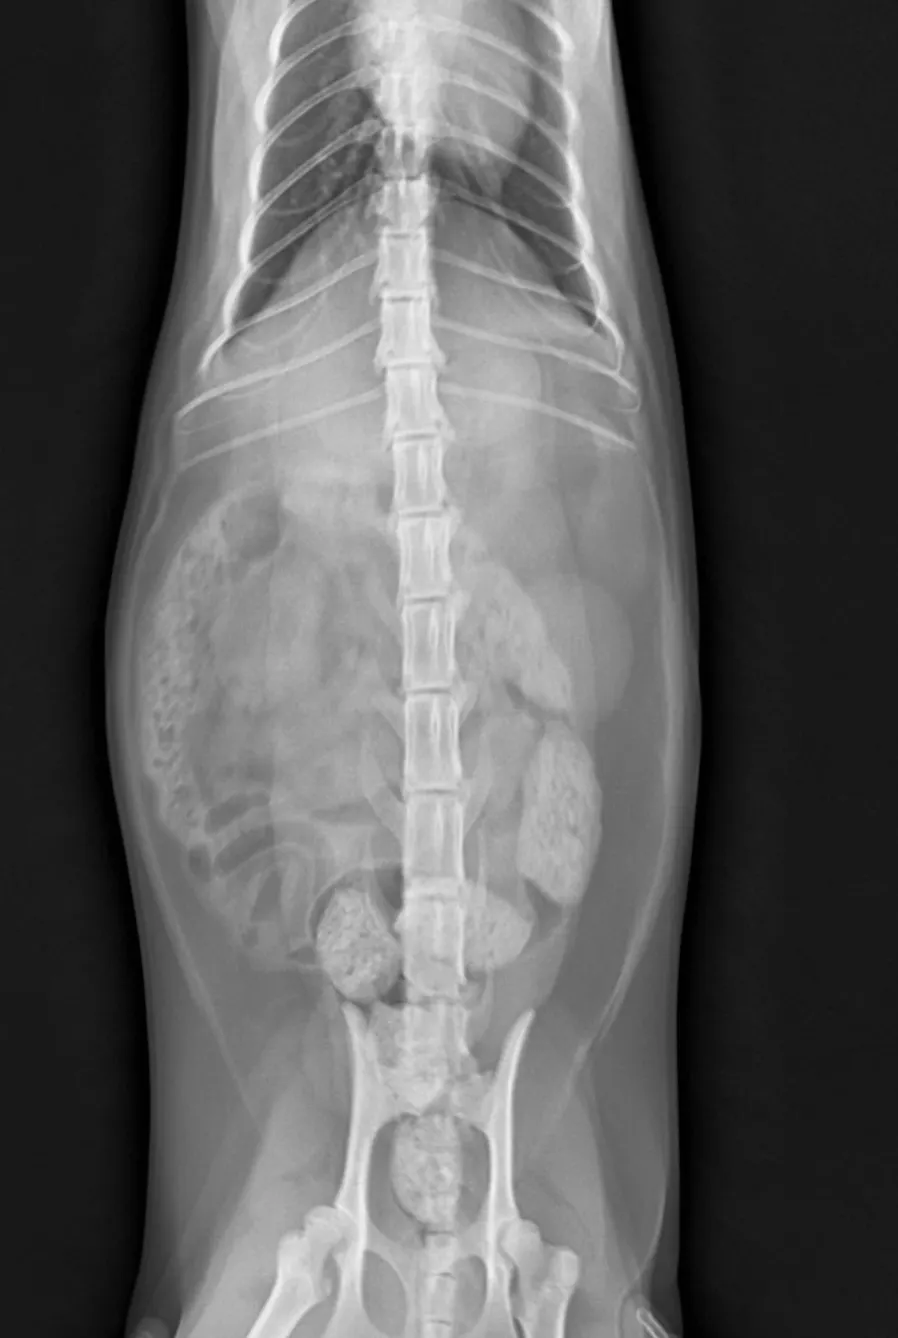

3) 골반 방사선 검사

곰이의 경우 골반을 추가로 방사선 검사를 시행했는데, 전공의 소견을 보면 다음과 같습니다.

좌측 femoral head의 coverage는 mild한 정도로 감소되어 관찰되며 양측 acetabular는 shallow하게 관찰된다.

우측 femoral head의 mild한 osteophyte.

주치의 소견을 말씀드리면

곰이는 양측 고관절에 관절이상 소견이 미약하게 관찰됩니다. 선천적으로 고관절이 안좋은 경우는 간혹 발생하며 나이가 들면서 진행될 수 있기 때문에 1년에 한번씩 고관절에 대한 방사선 평가를 해보는 것이 좋습니다.

체중이 많이 늘면 좋지 않으며 과도한 점프나 운동은 좋지 않습니다.

뒷다리 파행 증상 보일경우 내원해서 확인이 필요합니다.